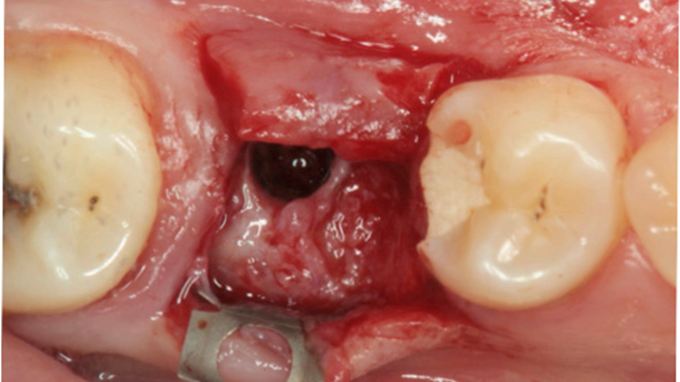

Clinical case: # 46 implant placement & GBR using i-Gen membrane for significant vertical resorption & mixed bone defect

- Courtesy of Dr. Iulian Filipov, Romania -

AnyRidge, mandibular posterior, i-Gen, resorption, bone defect, bone regeneration, space management, #46, GBR, Dr. Iulian Filipov

AnyRidge implant system, i-Gen